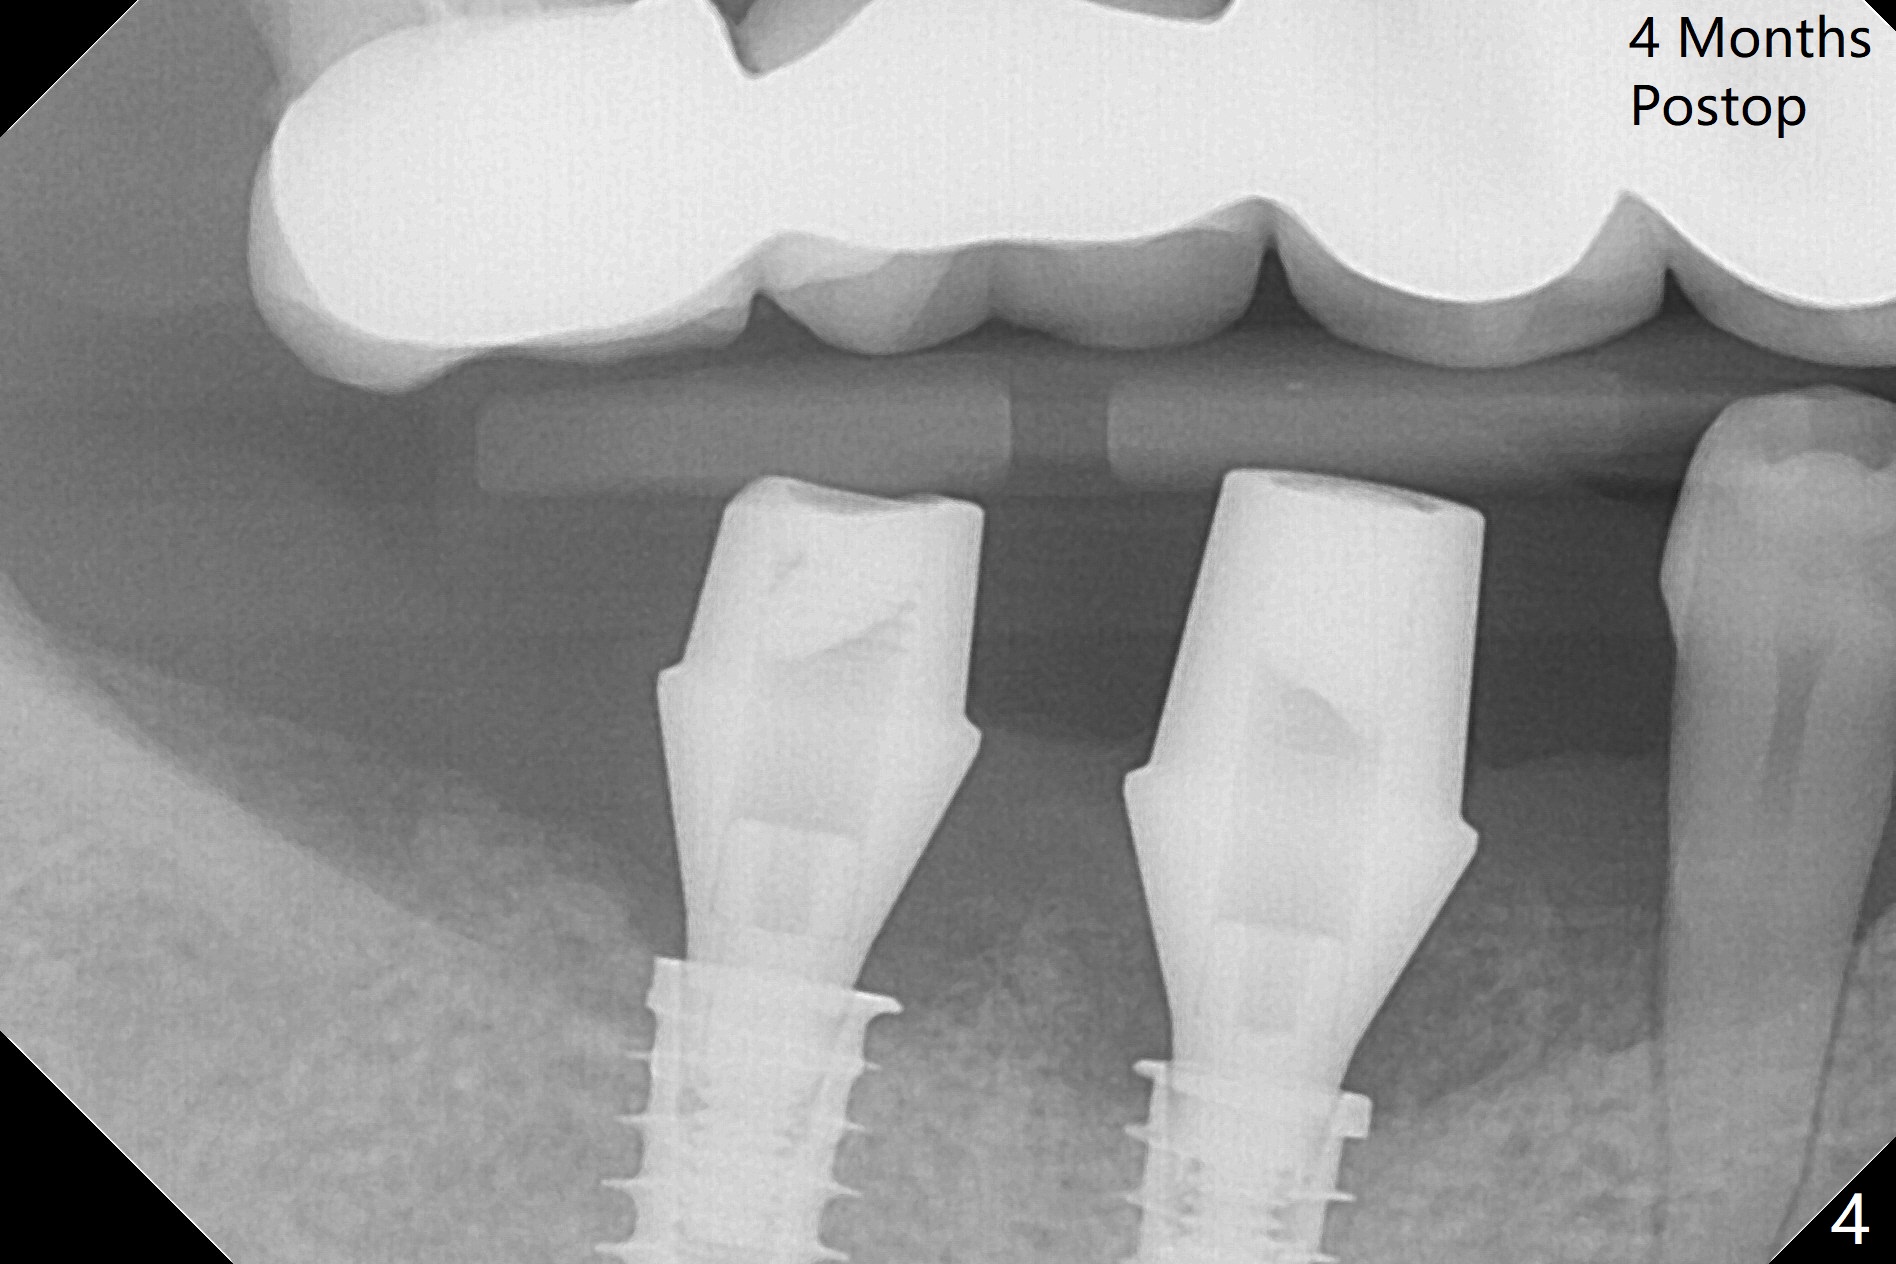

Following osteotomy, 4.5x11 and 5x9 mm dummy implants are placed at the sites of #30 and 31, respectively (Fig.1). Due to limited inventory of Magicore and patient's in-cooperation, FC implants (4.5x9 and 5x9 mm) are placed (Fig.2). A healing abutment (6x4 mm) is placed at #31 because of low torque (overprep), while a pair abutment (6.5x5.7(4) mm) is placed at #30. Vera Graft is placed with autogenous bone (*). The implant/abutment ratio at #30 is unfavorable. If the implant turns out to be loose, immediate implant should be larger in the future. Note bone growth, especially at #30, 2.5 and 4 months postop (Fig.3,4). In fact the abutments are incompletely seated. The crown of #30 is loose 2 years 8 months post cementation, while the abutment at #31 remains incompletely seated (Fig.5). The latter is completely reseated after separating the crown, while a smaller one is seated at #30 (Fig.6) due to use of a small healing abutment earlier (Fig.5). A good piece of news is the presence of the bone between the implants (Fig.5,6 *), which contributes to interimplant papilla. Return to Lower Molar Immediate Implant, Prevent Molar Periimplantitis (Protocols, Table), IBS77, 2-5 Xin Wei, DDS, PhD, MS 1st edition 09/22/2017, last revision 12/01/2020